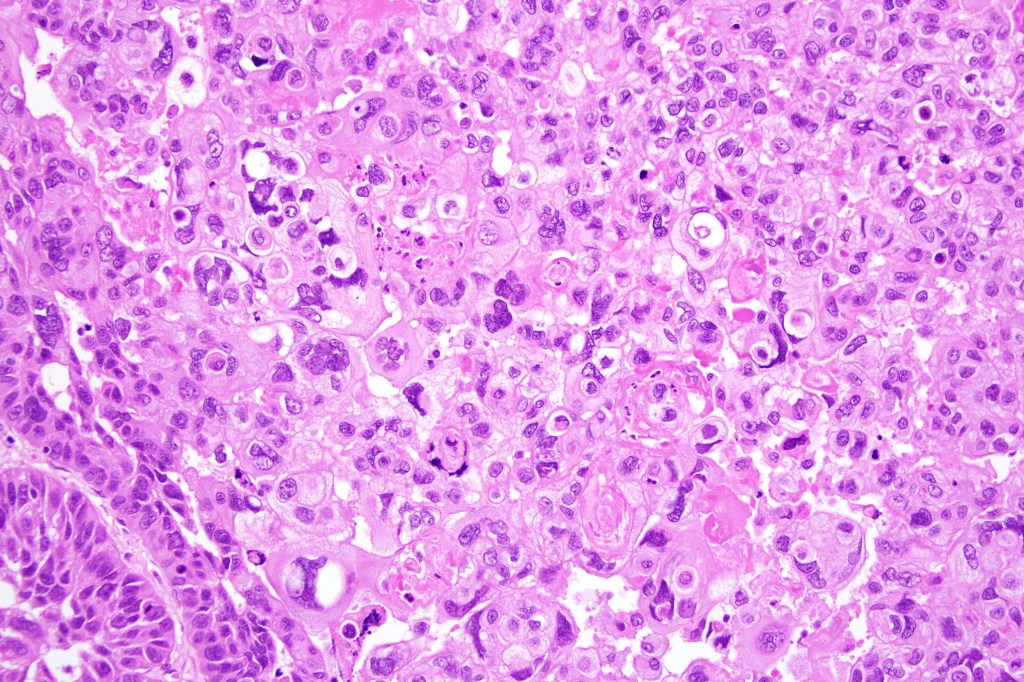

•Clear cell change results from cytoplasmic glycogen accumulation

•Can be focal or involve most of the tumor

•Exceptionally, this can present with a signet ring-like appearance